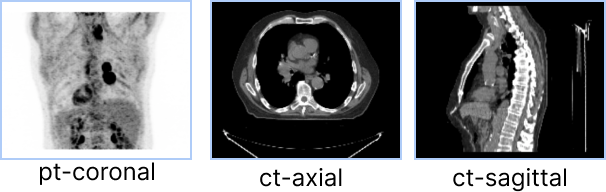

Consider the following set of viewports, and the desired behavior for scrolling and panning.

For ct-axial and ct-sagittal viewports, we want to enable scrolling by mouse wheel and panning by mouse middle button drag.

However, for the pt-coronal which is a Maximum Intensity Projection (MIP) viewport, scrolling through slices

has no meaning, and desired behavior is to rotate the MIP volume by mouse wheel and disable panning.